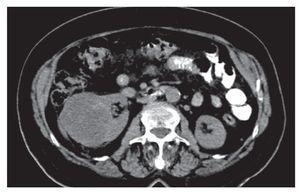

Mujer de 69 años de edad, originaria del Estado de México, portadora de hipertensión arterial de ocho años de evolución con adecuado control; refirió el antecedente de funduplicatura laparoscópica en junio de 2008 por diagnóstico de reflujo gastroesofágico. Durante su seguimiento por cirugía general se solicitó tomografía, en la que se documentó hallazgo incidental de tumoración renal derecha de 5 cm por 7 cm (Imagen 1), motivo por el cual fue referida a nuestro servicio. La paciente se mantuvo asintomática desde el punto de vista urinario; la exploración física no dio datos relevantes para el diagnóstico de referencia. Se completó el protocolo prequirúrgico y se sometió a nefrectomía radical derecha el 10 de abril de 2010, sin complicaciones trans o posquirúrgicas, fue egresada al tercer día del posoperatorio. El informe histopatológico fue: Producto de nefrectomía derecha, con neoplasia benigna morfológicamente consistente con oncocitoma renal de 7 cm de diámetro mayor, con hemorragia reciente multifocal, cápsula renal libre de lesión, limite quirúrgico viable, parénquima residual no neoplásico con pielonefritis crónica (Imagen 2); se realizó tinción especial de hierro coloidal la cual fue negativa, confirmando el diagnóstico de oncocitoma renal.

Imagen 1. TC del paciente, en foco renal. Se evidencia tumoración dependiente del riñón derecho, sin afectación linfática regional.